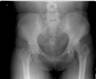

Post

Op

Xrays